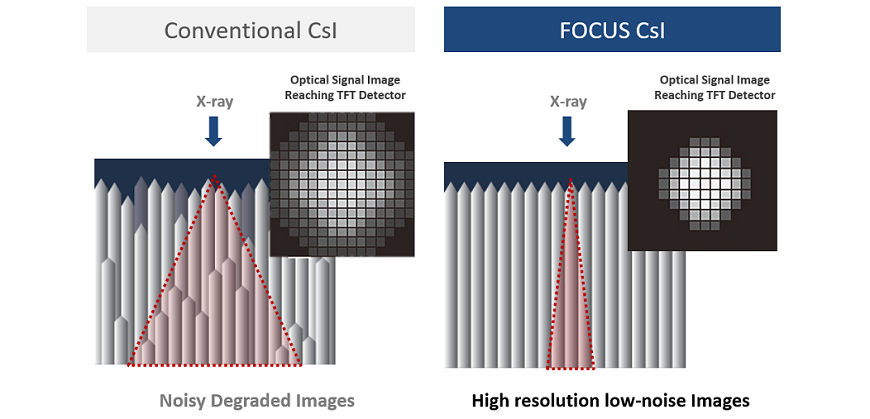

Tecnología de centelleo de enfoque

FOCUS (estructura mejorada CsI óptica fluorescente) tiene una señal óptica más enfocada en comparación con CsI convencional. Como resultado, la tecnología FOCUS logra un ruido ultrabajo.

2 veces mayor DQE en dosis bajas